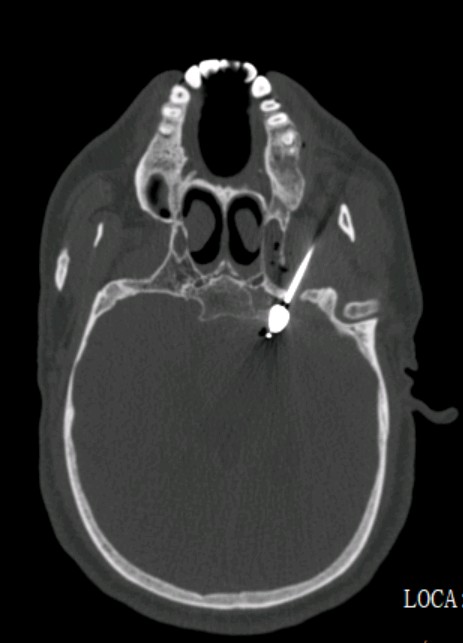

根据疼痛部位和疼痛的特点,结合三叉神经MRTA检查,王先生被诊断为三叉神经痛(V1)。一开始药物治疗有效果,疼痛有所缓解,但是一段时间后药物也不能控制疼痛了,王先生被收住入院。